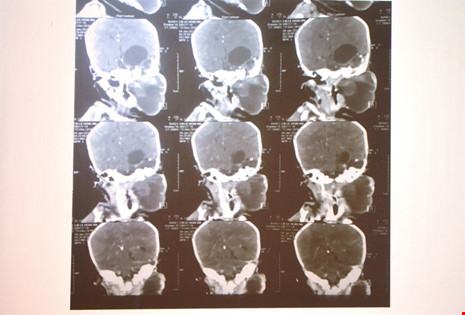

Ngày 20/1, BS Phan Minh Trí, Khoa Ngoại tổng hợp, BV Nhi đồng 1 TP HCM cho biết, vào tuần trước BV vừa tiếp nhận một bé gái khoảng 20 ngày tuổi trong tình trạng có một khối bướu ngay góc hàm bên trái.

Qua chẩn đoán hình ảnh, khối bướu nằm từ góc hàm nhưng lan lên vùng nội sọ. Nếu không được phẫu thuật sớm, em bé có thể tử vong vì nguy cơ khối bướu chèn ép đường thở gây suy hô hấp hoặc chèn ép đường ăn.

Mặt khác, vùng bướu lan lên nội sọ có thể tăng sinh, gây chèn ép vào phần não còn lại. Theo đánh giá, đây là một loại bướu vô cùng hiếm từ trước đến nay, y văn thế giới chỉ mới ghi nhận một trường hợp tương tự ở Mỹ và VN là trường hợp đầu tiên.